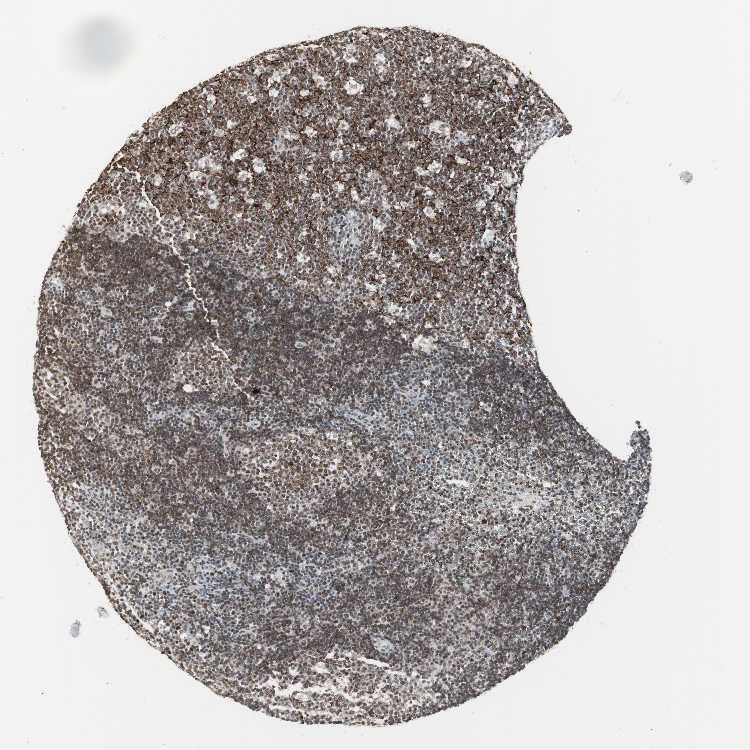

TISSUE PRIMARY DATA LYMPH NODE Show tissue menu

LYMPH NODE - Antibody stainingi

Antibody staining in the annotated cell types in the current human tissue is reported as not detected, low, medium, or high, based on conventional immunohistochemistry profiling in selected tissues. This score is based on the combination of the staining intensity and fraction of stained cells.

Each image is clickable and will lead to virtual microscopy that enables deeper exploration of all samples and also displays staining intensity scores, fraction scores and subcellular localization as well as patient and tissue information for each sample.

Antibody HPA006714Antibody CAB079946Antibody CAB079947

Germinal center cells HighMediumMedium

Non-germinal center cells HighMediumMedium